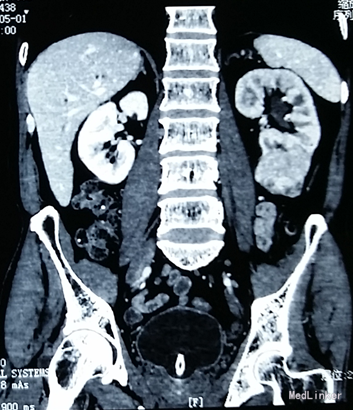

患者,男性,62岁,因“无痛性血尿1月”入院。既往史:30年前有肺结核病史。个人史:30年抽烟史,平均1包/天。

查体:一般生命体征平稳,左侧肾区叩击痛(+)。 辅助检查:血生化:肌酐101umol/L。 泌尿系彩超:左肾实性占位(74x48mm) 双肾ECT:肾小球滤过率(GFR)左肾为29.77 ml/min,右肾为43.67 ml/min。左肾总体灌注正常,功能轻-中度受损 心脏彩超):房间隔缺损(继发孔型),舒张期左→右分流,左室EF64%。 外院CT:左肾下极占位。

诊断:左肾占位性病变。 予完善相关术前检查,查无明显手术禁忌,予行腹腔镜下左侧肾部分切除术。 术后病理诊断:透明肾细胞癌。